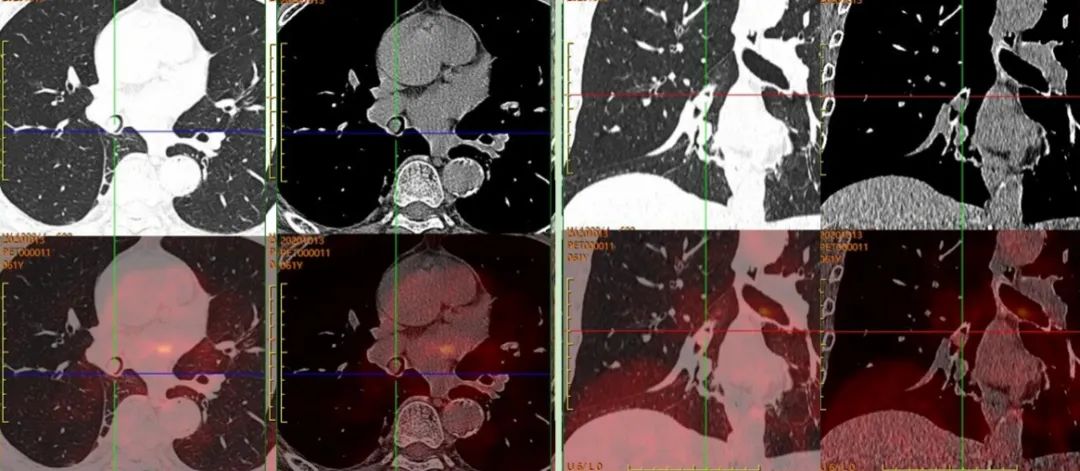

患者于上級(jí)醫(yī)院行氣管鏡檢查,病理考慮為“惡性腫瘤”。后來我院行PET/CT,完善治療前檢查。

圖2,PET/CT示右肺中間段支氣管結(jié)節(jié),早期SUVmax約1.8,延遲SUVmax約1.9,呈低代謝表現(xiàn);全身其余部位未見惡性腫瘤證據(jù);考慮為孤立的、單發(fā)的支氣管腔內(nèi)腫瘤,建議患者病理檢查。

患者后于上級(jí)醫(yī)院手術(shù)治療,術(shù)后病理為“支氣管錯(cuò)構(gòu)瘤”。